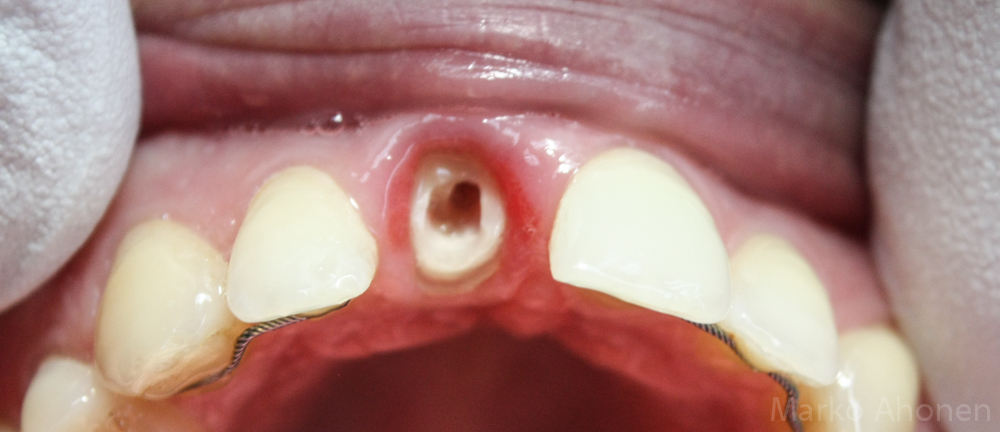

Implantti näkyvissä ikenen alla, paranemisruuvi on juuri poistettu:

Hampaan juuri oli kohtuullisessa kunnossa ja juurentäyte oli suojattuna erillisellä paikalla. Aikaisempi kruunu oli tuettu pienimmällä nastalla ja nyt ien oli selvästi kruunun alla:

IMG_0898 IMG_0899

Vaihtoehdoista pohdimme implanttia tai uuden keraamisen kruunun tekoa. Nopeuden ja hinnan puolesta päätyimme kuitunastapilariin ja keraamiseen kruunun. Hammas valmistettiin samana päivänä alusta loppuun asti.Kuitunastapilari ja sähköveitsellä siistitty ien. Ientä poistettiin runsaasti jotta hampaan kudos saatiin näkyviin. Luu jäi vielä 2mm päähän joten biologista leveyttä ei rikottu vaikka rajalle mentiinkin.